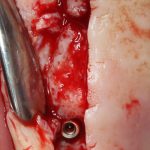

Трансплантация десны, аугментация лунки

Для определения размеров будущего мягкотканного аутотрансплантата мы использовали пародонтологический зонд. С помощью него мы выбрали донорскую зону (бугор верхней челюсти или небная сторона альвеолярного отростка верхней челюсти в области моляров), с помощью скальпеля получили необходимый по размеру аутотрансплантат (мягкотканный лоскут для пересадки).

Затем, мы подготовили ксенографт Bio-Oss Collagen. Обычно на 2 зуба (центральных резца) с избытком хватает 100-миллиграмовой упаковки. Имеющийся в ней параллелепипед мы поделили на 2 усеченные пирамиды с основанием в 2/3 ширины изначального блока.

Если вы когда-нибудь видели подобные операции, то наверняка обращали внимание на порядок действий — сначала устанавливаются имплантаты, затем укладывается графт и только потом фиксируется мягкотканный аутотрансплантат. Для удобства в этом и похожих клинических ситуациях мы поменяли порядок действий:

Сначала мы провели и зафиксировали деэпителизированный соединительнотканный аутотрансплантат (ССТ). Для этого мы сформировали тоннель и использовали ортодонтическую проволоку в качестве проводника. Подробнее об этой методике можно почитать здесь>>.